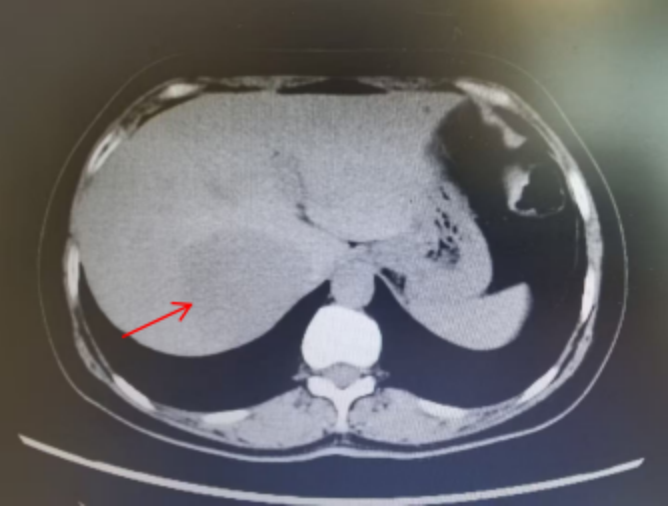

腹部 CT 与磁共振检查结果印证了担忧:刘大叔肝右叶存在一个 7.0 公分大小的肿物,考虑为原发性肝癌,肿瘤位置特殊——位于肝 VII 段,深嵌于肝脏内部,与肝右静脉、肝中静脉及下腔静脉等大血管紧密相邻。这一区域被业界视为腹腔镜肝切除的「困难区」,手术中稍有不慎便可能损伤大血管,引发大出血,同时还需在彻底切除肿瘤的基础上,最大程度保留残余肝脏功能,避免术后肝功能衰竭,手术方案制定面临双重考验。